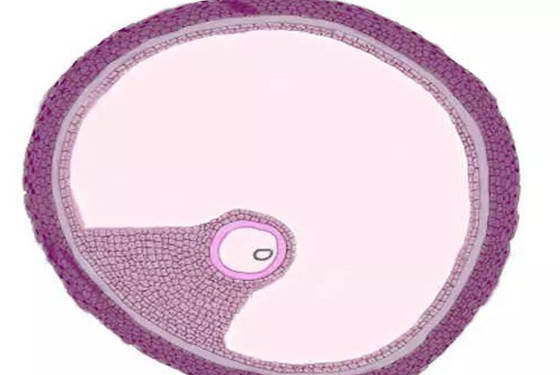

卵泡期,是女性特有的生理时期,它是指从月经第3天至排卵当日的时段,一般女性的排卵期和黄体期是重合的,主要指月经来潮前14天的时间段。

并且女性特有的卵泡期也分为三个不同的阶段,即滤泡早期(月经第3-4天);滤泡中期(第9-10天左右);卵泡成熟期(第12-14天)。

每一个阶段有所不同,通过B超仪器可以很准确的观察到这三个阶段的变化发展情况。女性的卵泡期正常与否很重要,这关系到能不能正常排卵,能不能顺利受孕的问题。